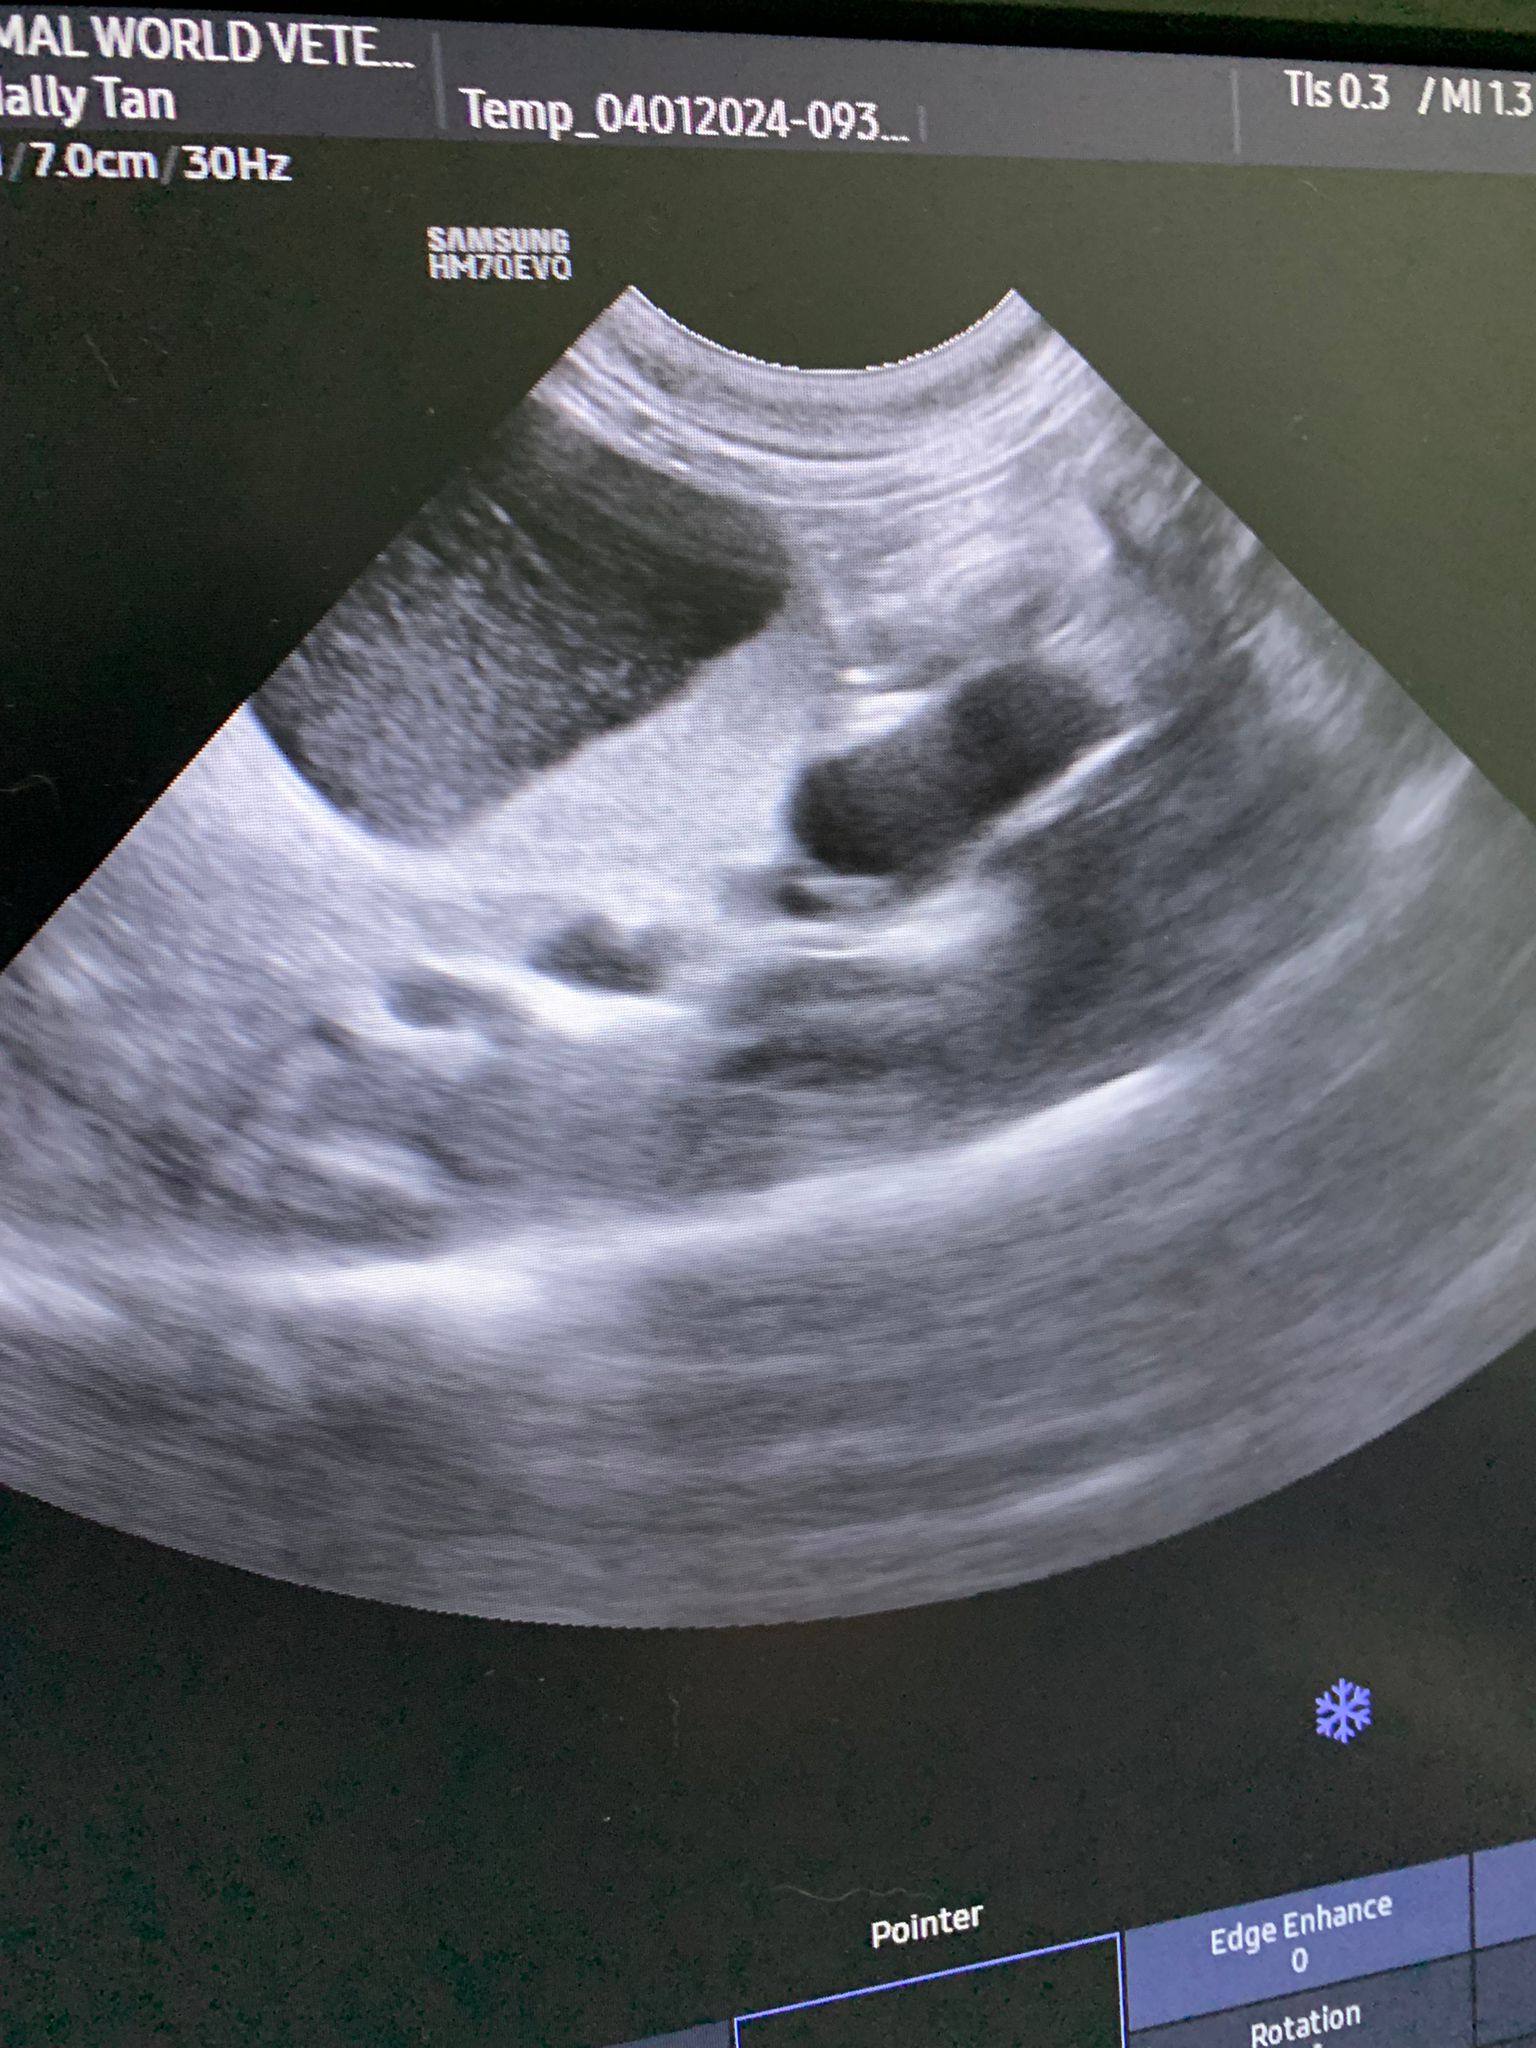

11.28am: Scarlett bring her into the room for abdominal u/s.

U/s done and basically not much use to me, liver got issue, kidneys got some fatty deposits which is diabetic, so insulin correct. Gall bladder got some obstruction so just start urofalk. All in must put o tube. Dr Daniel do it.

Dr ym scan sweeties, dr flo not involve, both got free fluid ard the kidneys, left kidney is extremely abnormal, right kidney abnormal.

U/s still show the scary fluid ard the kidneys and there is issue w gall bladder also. As the GGT 7 but without confirming is it an obstruction cannot anyhow use. Give le obstruct will rupture.